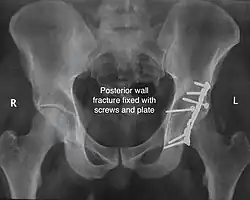

Posterior wall This is the most common variety of acetabular fracture. It typically occurs due to dashboard injury; when a person travelling in a vehicle involved in a head-on collision, the force applied over the flexed knee travels along the femur bone to the head of the femur, breaking the posterior wall of the acetabulum. The head of the femur is dislocated outside the joint. T shape When a transverse fracture also had a vertical fracture line, it is called a T shape fracture. Here the innominate bone is broken in such a way that all three parts of it, the ilium, the ischium and the pubis are separated from one another. This is a three part fracture. Though both columns are broken, the weight bearing dome is still attached to the main part of the ilium and hence it is not a true fracture of both columns.

The final management depends on the size of the fragment(s), stability and congruence of the joint. In some cases traction for six to eight weeks may be the only treatment required; however, surgical fixation using screw(s) and plate(s) may be required if the injury is more complex. The latter treatment will be called for if bone fragments do not fall into place, or if they are found in the joint, or if the joint itself is unstable.

• Kocher Langenbeck approach for posterior injuries